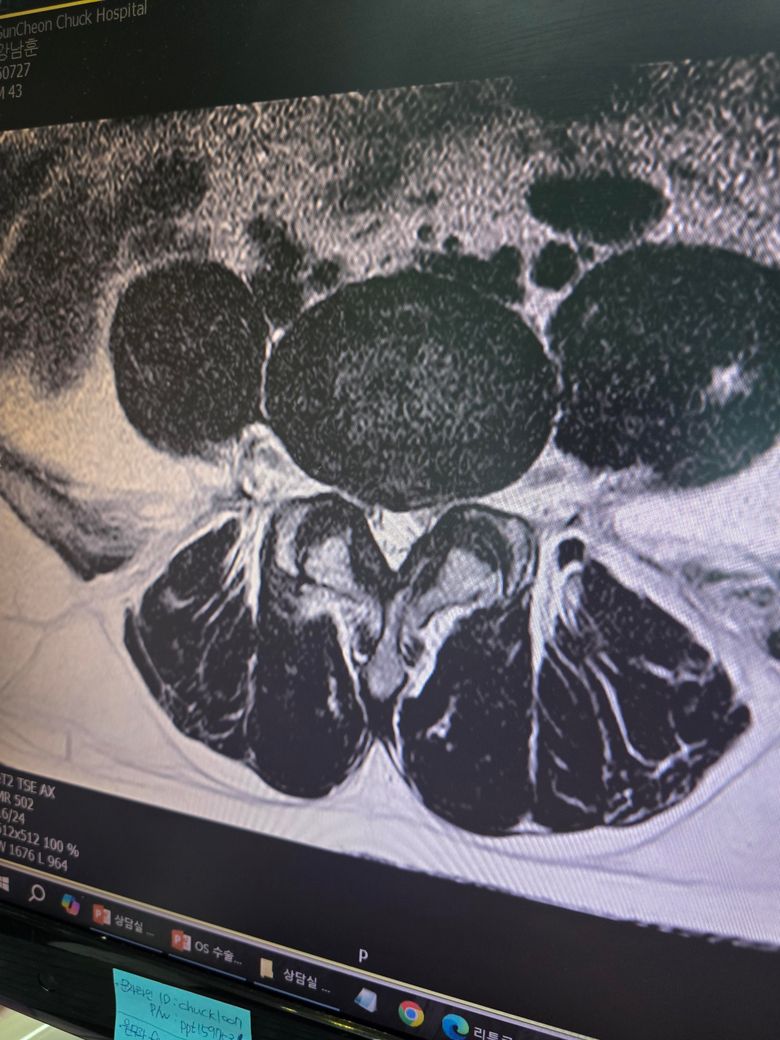

요추4,5 디스크 판정인데 수술을 권유하시는데 그정도로 안좋은 상태일까요?

증상은 앉을때나 누울때는 전혀 통증이 없고 허리를 펴고 일어서 있거나 걸을때 엉덩이에 방사통이 심한 편입니다

허리에 통증은 크게 없구요

서서 허리를 숙이거나 쪼그려 앉으면 통증 완화가 되긴 한데 허리를 피면 엉덩이에 방사통이 심하네요

금일 mri 촬영했는데 시술이나 보존치료가 아닌 단방향내시경수술을 권하시네요

시술단계가 아닌 수술이라는데 그정도일까요?

통증으로는 잠시 서있는것도 힘들만큼 아프긴 합니다ㅠ

• 1번 째 사진